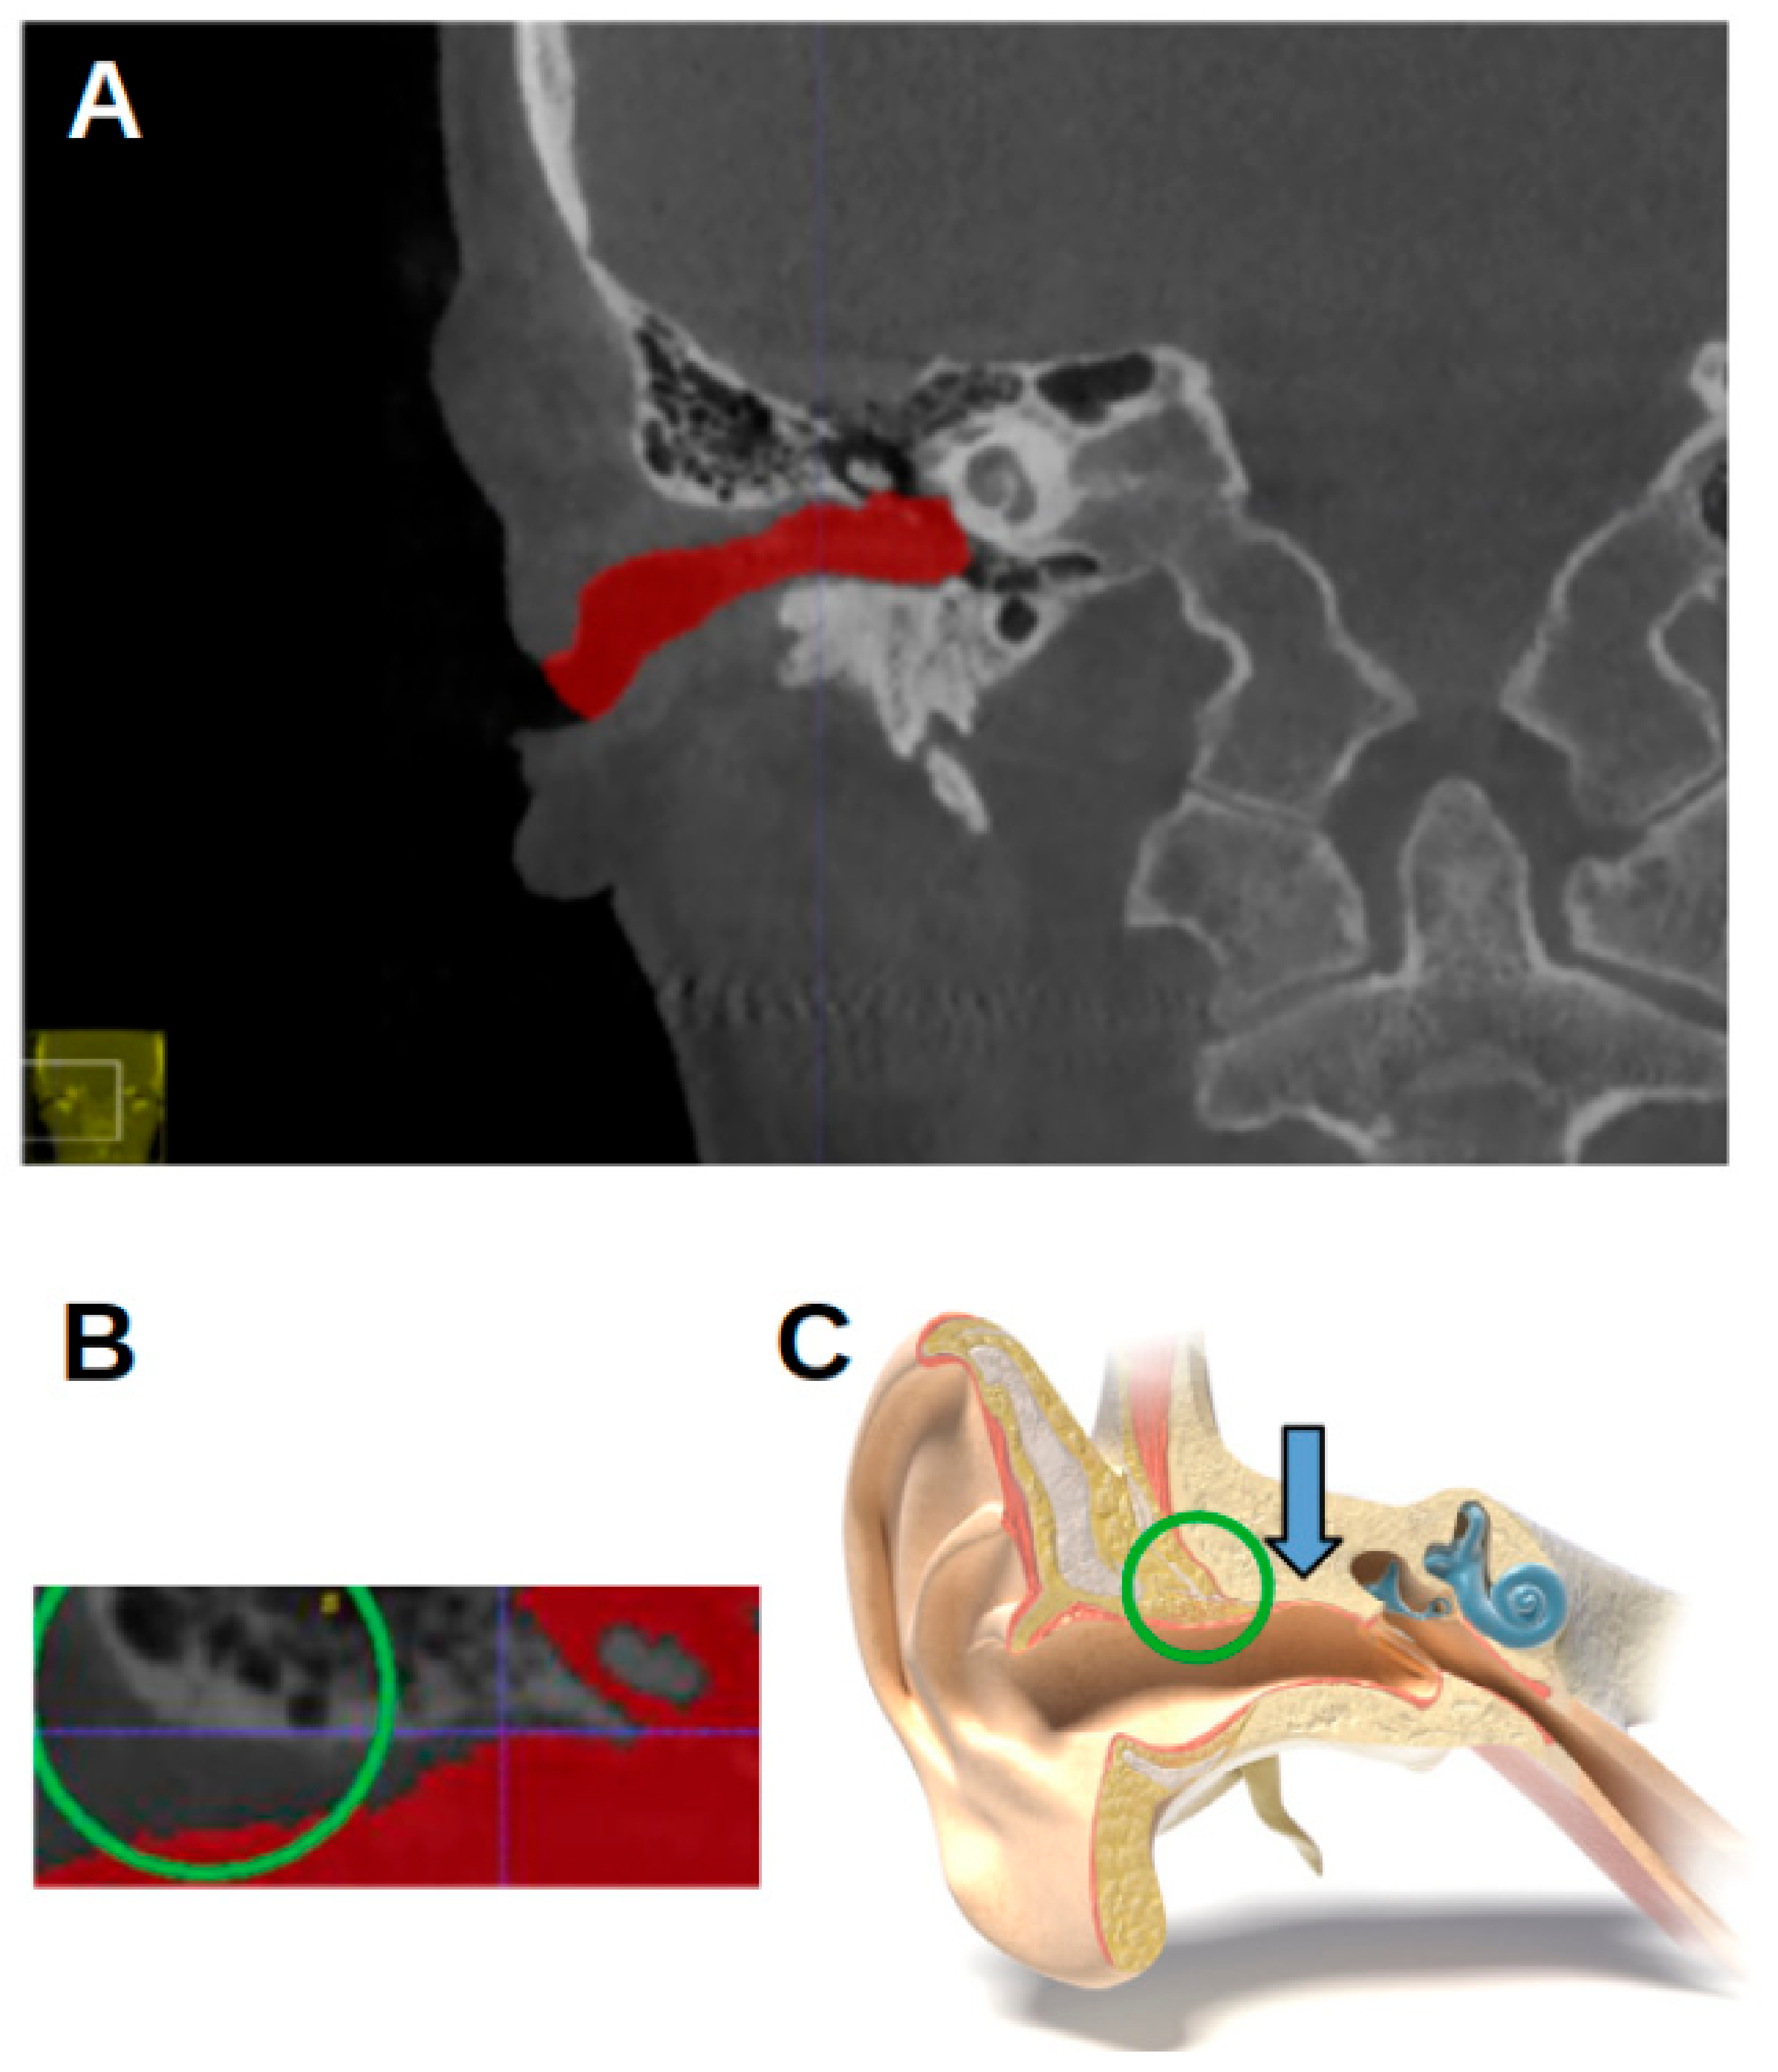

The CBCT images were represented on the computer as DICOM (Digital Imaging and Communication in Medicine) files. The CBCT images were analyzed using ITK-SNAP software, version 3.8, University of Pennsylvania, Philadelphia, PA, USA, (www.itksnap.org, (accessed on 17 June 2023)) [15]. The acoustic meatus were segmented using the “active contour segmentation mode”, which enabled ITK-SNAP to differentiate between different structures according to the grayscale of the image. The segmented acoustic meatus on the right side were labeled with a red color (label 1), and those on the left with a green color (label 2). Figure 1 shows an example of the segmentations.

Figure 1. Three-dimensional reconstruction of the acoustic meatus. (A) A representation in ITK-snap. (B) Coronal view of the segmentations of the right (red) and left (green) meatus, with the EAM flowing into the cauliflower-like shape representing the internal acoustic meatus.